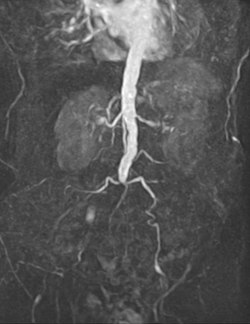

An abdominal aortic aneurysm (AAA) refers to aneurysmal dilation of the aorta confined to the abdominal cavity. Most commonly, aneurysms are asymptomatic and located in the infrarenal position. Often, they are discovered incidentally or on screening exams in patients with risk factors such as a history of smoking. Patients with aneurysms which have a diameter less than 5 cm are at <1% rupture risk per year. When the aneurysm meets size criteria it can be treated with aortic replacement or EVAR.

Abdominal aortic aneurysms can be classified as infrarenal, juxtarenal, pararenal or suprarenal as depicted in the illustration.